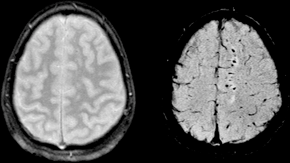

Susceptibility weighted image (SWI) of diffuse axonal injury in trauma at 1.5 teslas (right)